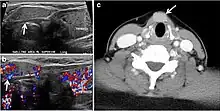

Fig. 4. A 45-year-old male patient presented with anterior mediastinal metastatic PTC lesions and occult primary on imaging. Histopathology examination of the resected thyroid gland revealed micro-foci of PTC; the largest, in the isthmus, measured 4 mm. a transverse greyscale ultrasound of the thyroid demonstrates homogeneous gland with normal echogenicity and size. No focal lesion or micro-calcifications. b Non-enhanced CT scan obtained as part of PET/CT examination shows a heterogeneous, large, relatively dense anterior mediastinal mass (white arrow) with peripheral calcification (arrowheads). Thyroid gland has normal CT appearance with no abnormal FDG uptake (not shown).[1]

Fig. 7. A 51-year-old female patient post total thyroidectomy for PTC with elevated thyroglobulin measurement. an Axial non-enhanced CT scan of the neck at the level of the thyroid bed demonstrates a well-defined, rounded, homogenously dense soft tissue situated between the trachea and left internal jugular vein (white arrow). b Transverse ultrasound image of the neck demonstrates a well-defined, homogeneous, hypoechoic soft tissue nodule measuring 6 mm (white arrow) with no detected micro-calcifications. Biopsy showed a predominantly residual normal thyroid tissue with micro-foci of PTC.[1]

Fig. 8. A 48-year-old male patient post total thyroidectomy with PTC recurrence. a Transverse greyscale ultrasound of the neck demonstrates a left thyroid bed heterogeneous, predominantly hypoechoic irregular lesion with calcifications (white arrow). b A spot image of iodine 123 total body scan of the neck demonstrate a focus of abnormal radiotracer uptake at the left thyroid bed (Black arrows) between the annotated markers. c Enhanced axial CT scan of the neck demonstrates an enhancing large left thyroid bed mass (white arrow) with no calcifications. The lesion exerts a mass effect on the oesophagus (black arrow) and is inseparable from the trachea.[1]

Fig. 9. A 58-year-old male patient with persistence PTC at thyroid bed with hypervascular nodal metastasis. a–c Transverse greyscale and colour Doppler neck ultrasound demonstrate hypoehoic soft tissue in the left thyroid bed (white arrow in a). There are a heterogeneous enlarged lymph nodes at level 2 and 3 with markedly increased vascularity (white arrow in b and c). d–f Enhanced axial CT images of the neck demonstrate a 2.7 × 1.4 cm hypodense soft tissue lesion anterior to the left carotid sheath (white arrow). There are left-sided enhancing abnormal and enlarged lymph nodes at cervical level 2 and 3 (black arrows).[1]